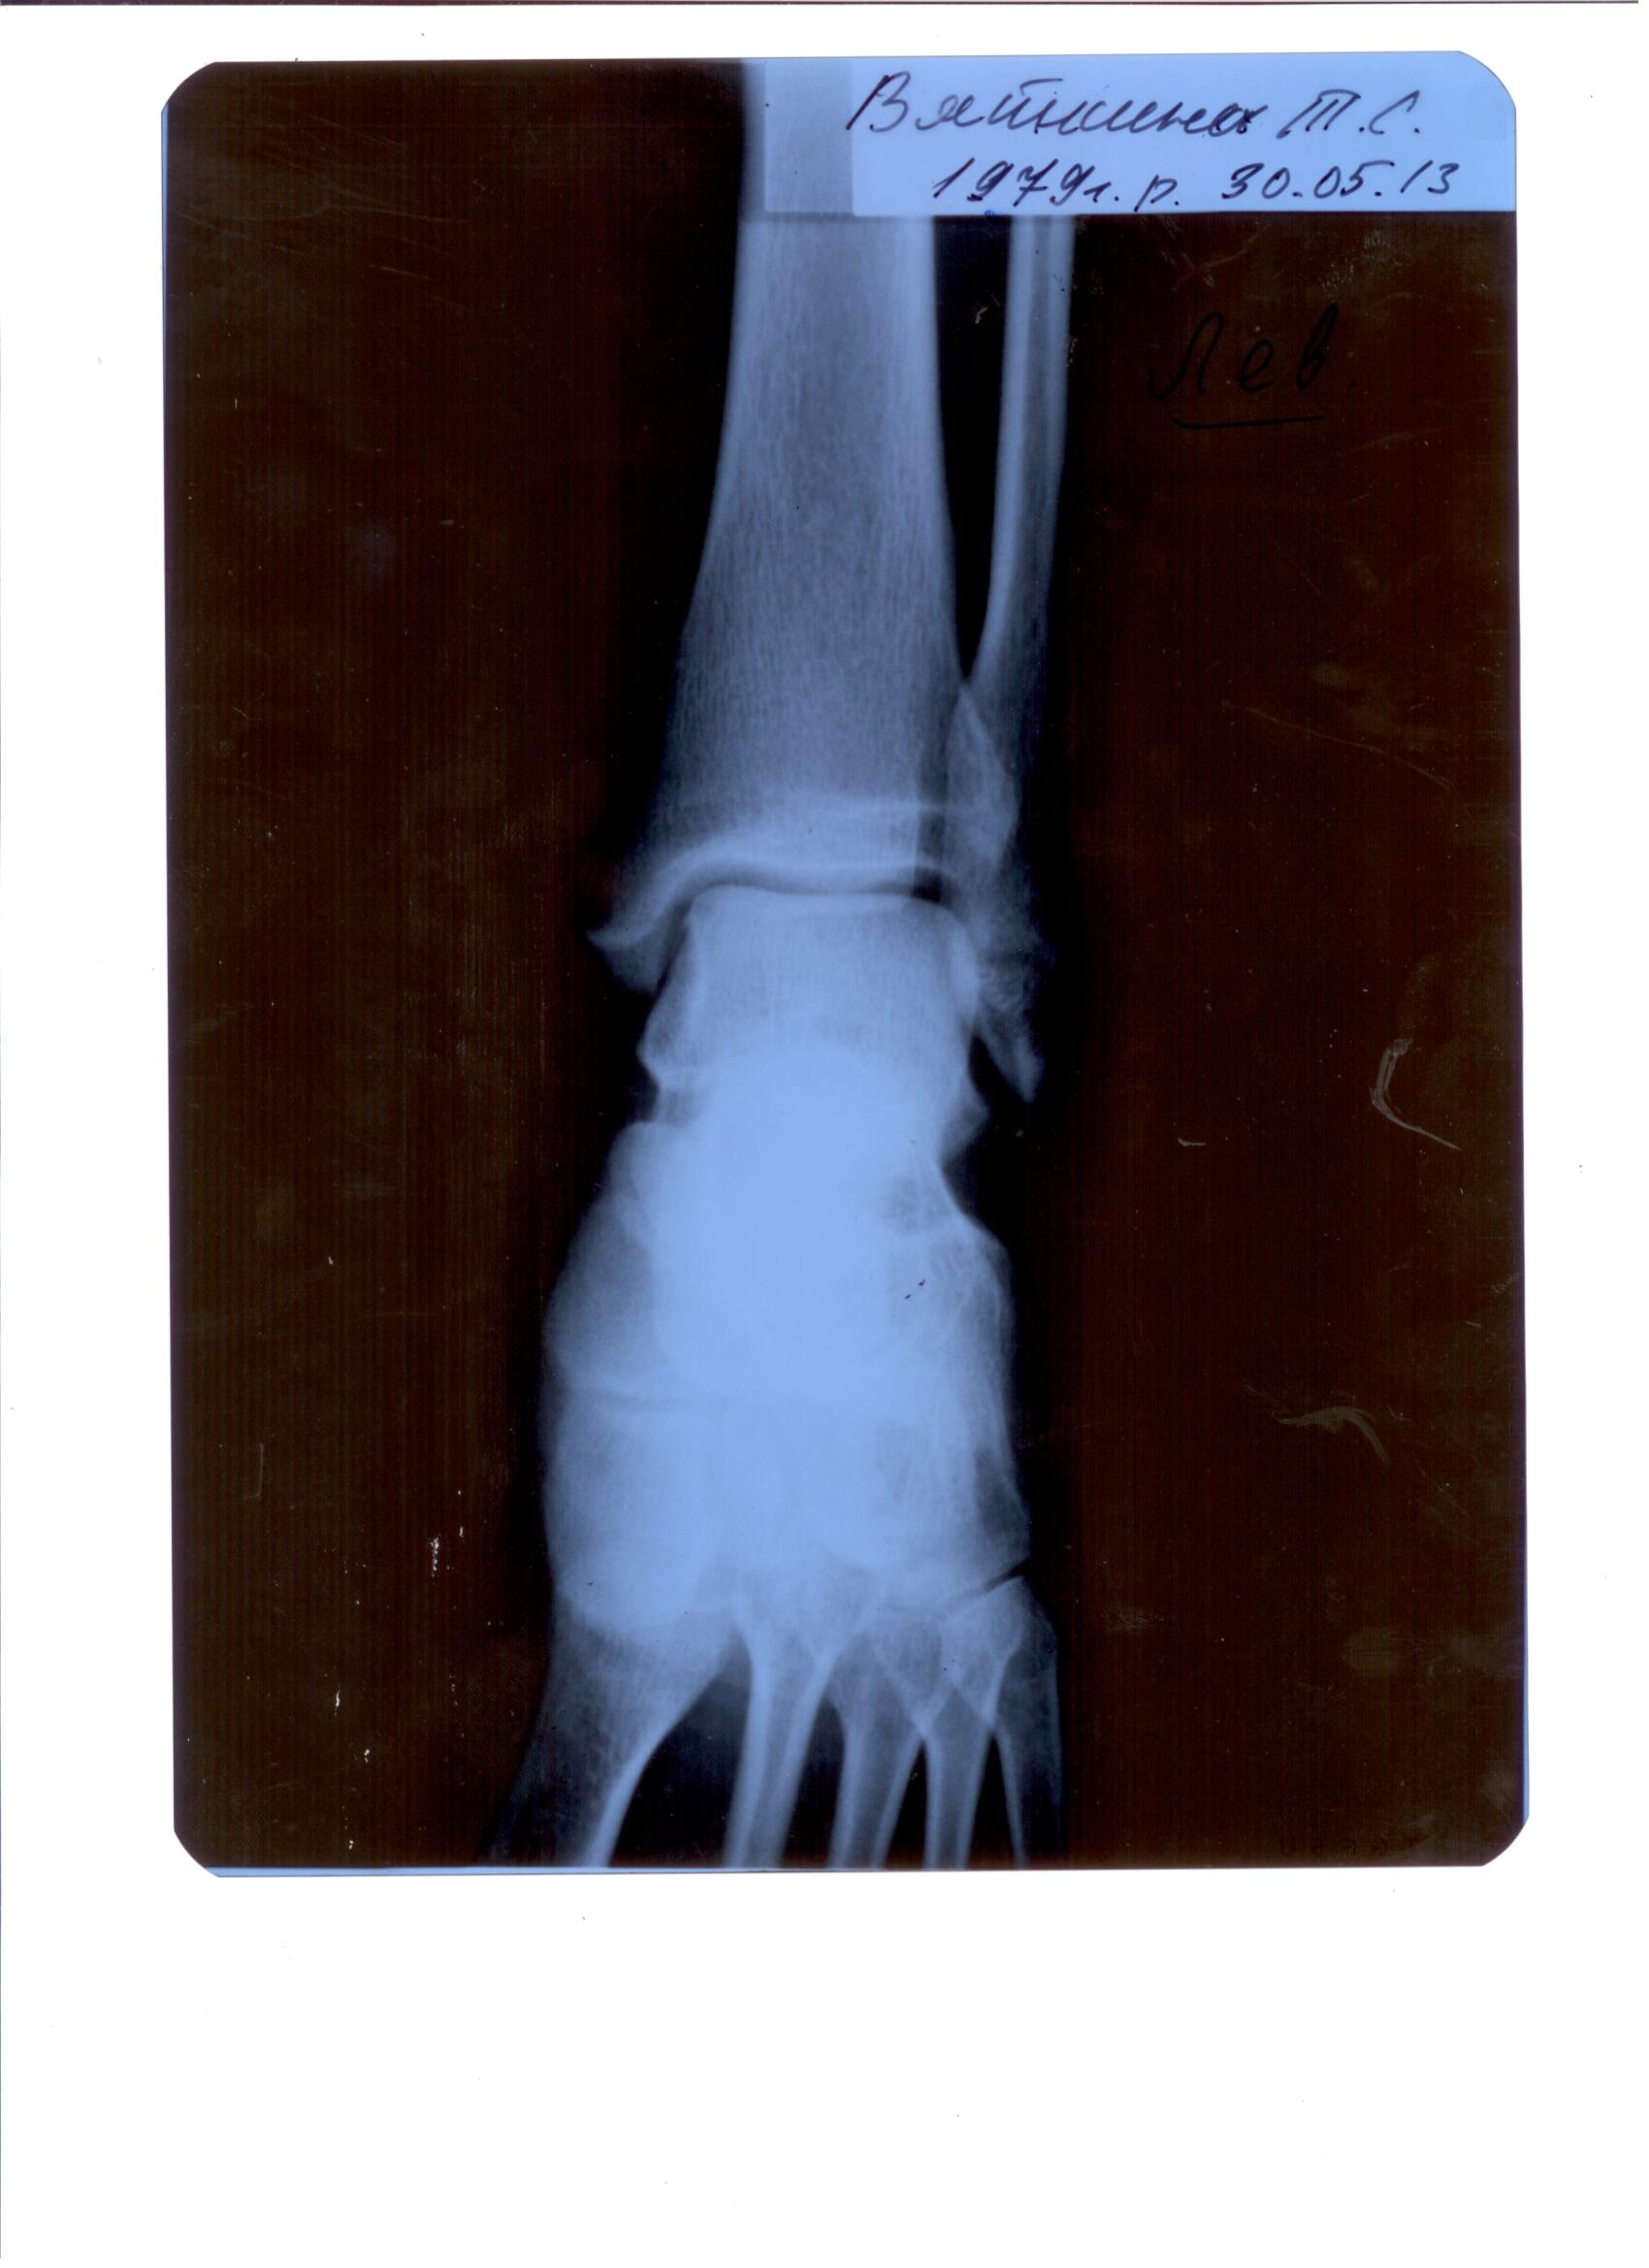

была полученная спортивная травма голеностопа, после рентгена, диагноз - перелом малоберцовой кости. после МРТ получено следующее заключение:МР признаки частичного повреждения нижних отделов сухожилия длинного сгибателя большого пальца, длинного сгибателя пальцев стопы. Частичное повреждение задней таранно-малоберцовой связки. Консолидирующийся краевой перелом дистального эпифиза малоберцовой кости. Синовит левого голеностопного сустава. Подскажите пож-та необходимо ли при таком диагнозе оперативное вмешательство?

Татьяна 12 Июль 2013, 09:28

травма была получена 3 апреля (на сборах)

ренген был сделан 30 мая

МРТ 03 июля

боль присутствует до сих пор, подвижность ноги сильно ограниченна.

Кликните для загрузки файла ренг.2.jpg